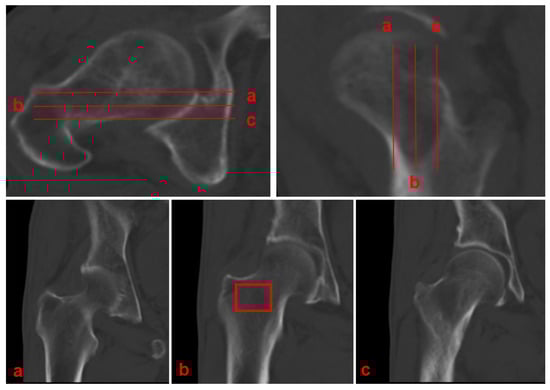

- Planar selection: Identify the coronal slice demonstrating the maximal cross-sectional area of intertrochanteric cancellous bone, which typically coincides with the central mechanical axis of the proximal femur.

- ROI placement: Position a rectangular ROI to fully encompass this cancellous bone area.

- Cortical exclusion: Carefully adjust the ROI to exclude the cortical bone boundaries.

- Data recording: Record the mean CT attenuation value (in Hounsfield Units) provided by the imaging software.